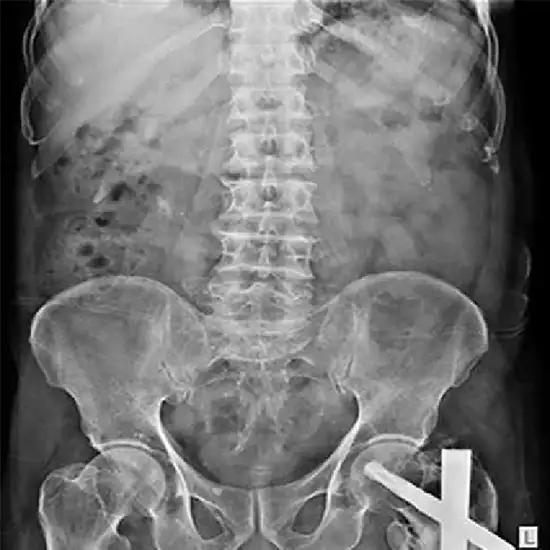

X-RAY LUMBER SPINE AP VIEW

The lower back, comprising the lumbar vertebrae (L1 to L5), intervertebral discs, and surrounding soft tissues, including muscles, can be seen with a painless and safe test called a lumbar spine X-ray.